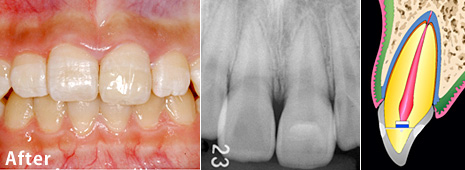

歯根破折の治療例

歯根破折の治療例 術前

術前:

31歳の女性の歯(歯根)が、けがで折れました。レントゲン写真でしか分かりませんが、歯は骨の中で折れています。でも、歯髄は生きていました。

歯根破折の治療例 術後

術後:

折れた歯を整復し(元通りの位置に戻し)、固定しました。この写真は術後6年です。いつもとは限りませんが、このように、歯根のところで折れても、適切な処置で歯を元通りにすることができます。